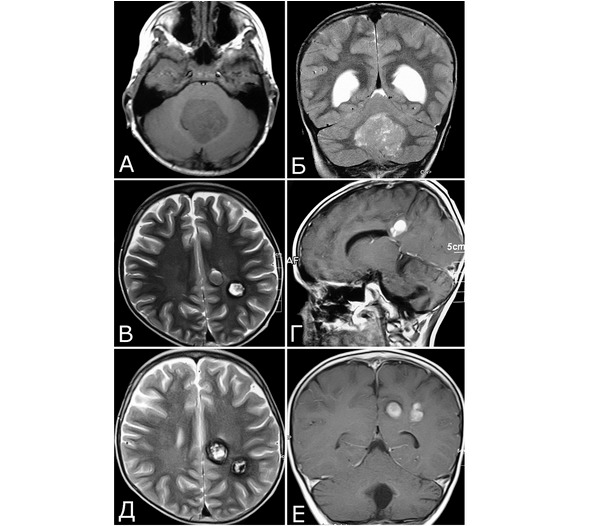

Рис. 27. Радиоиндуцированные кавернозные мальформации. Б-ной С-р, 2005 г. р. Клинический диагноз: медуллобластома IV желудочка. Состояние после удаления опухоли (2009 г) и адьювантной комбинированной терапии (лучевая терапия, 5 курсов химиотерапии). Радиоиндуцированные КМ. А, Б – 2009 г: крупная опухоль IV желудочка. МРТ, режимы Т1 и Т2. В, Г – 30.05.12г: при контрольном обследовании выявлены два бессимптомных объемных образования в правой теменной области, по МРТ—характеристкам соответствующие сосудистой патологии (радиоиндуцированные КМ?). Признаков рецидива опухоли нет. Д, Е – 10.05.13 г.: при контрольном обследовании объем и структура сосудистых образований остаются прежними. Учитывая отсутствие клинических симптомов, хирургическое вмешательство не проводили